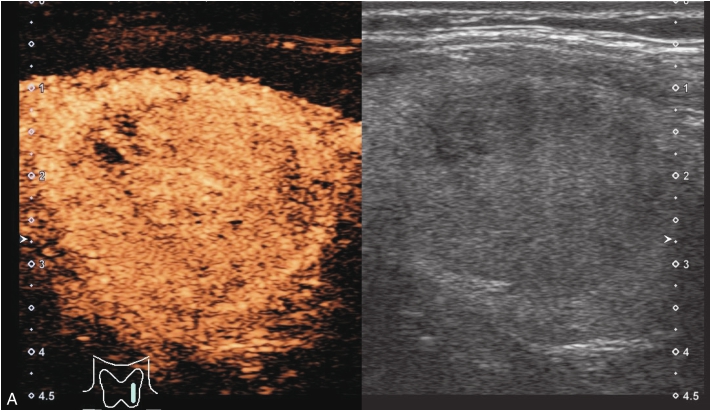

男性,52岁,外院发现甲状腺结节,为求进一步诊治收入我院。

甲状腺左叶中下部见一混合回声结节,边界清,形态规则,中心部可见斑状强回声,CDFI显示周边可见环状血流信号,其内可见丰富血流信号,见图1-3-18。

该结节早于周围腺体组织增强,结节内部呈高增强表现,可见部分无增强区;结节晚于周围腺体组织消退,仍呈高增强表现;结节周边可见均匀高增强环,甲状腺被膜未见明显中断,见图1-3-19、ER1-3-9。

(1)结节增强早期早于腺体增强或与腺体同步增强,增强晚期晚于腺体消退或与腺体同步消退。

(2)结节内部呈均匀或不均匀弥漫性等增强或高增强,增强水平通常高于周围腺体。

(3)结节与周围腺体分界清晰,形态较规则。

(4)部分结节周边可见均匀高增强环。

(5)结节周边被膜连续完整。

甲状腺滤泡性腺瘤通常为富血供病灶,其增强水平等于或高于周围腺体,并呈现“早增强,晚消退”的特点,重点需要与滤泡性腺癌鉴别,腺瘤多边界清晰、形态较规则,造影时结节周围的高增强环厚薄一致、较为均匀,结节周边被膜连续完整、无浸润表现,颈部淋巴结无异常肿大等。而滤泡性腺癌边界不清、呈浸润性生长表现,周边高增强环消失或厚薄不均,如发现颈部异常肿大淋巴结及被膜连续性中断等,需要高度警惕甲状腺恶性肿瘤。

图1-3-18 甲状腺滤泡性腺瘤常规超声声像图

A.甲状腺左叶纵切面超声图像;B.结节内部点状及斑状强回声;C.CDFI血流图